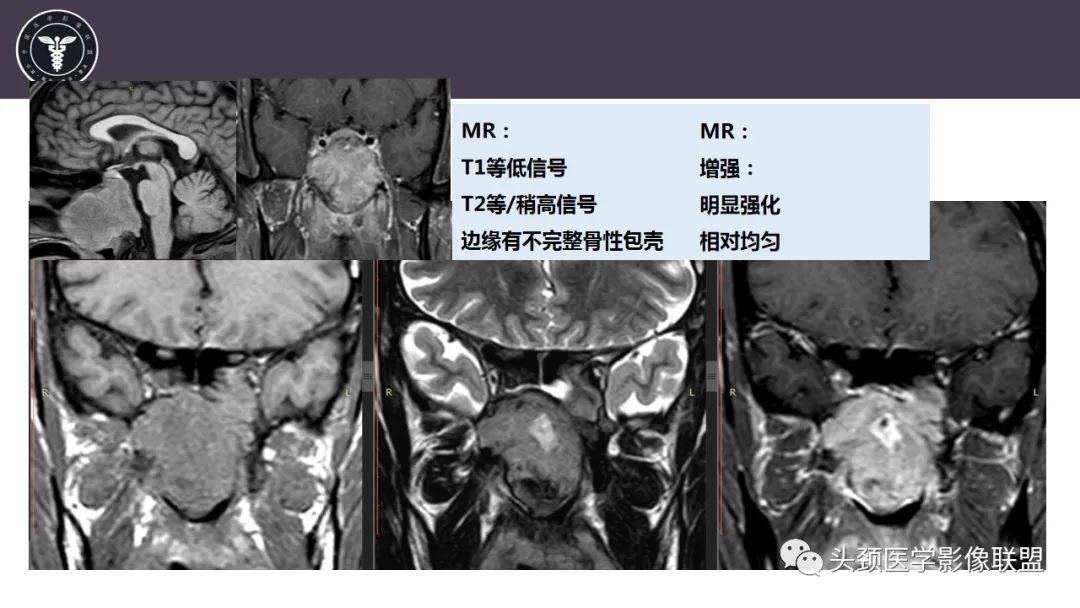

斜坡区骨巨细胞瘤 VS 脊索瘤